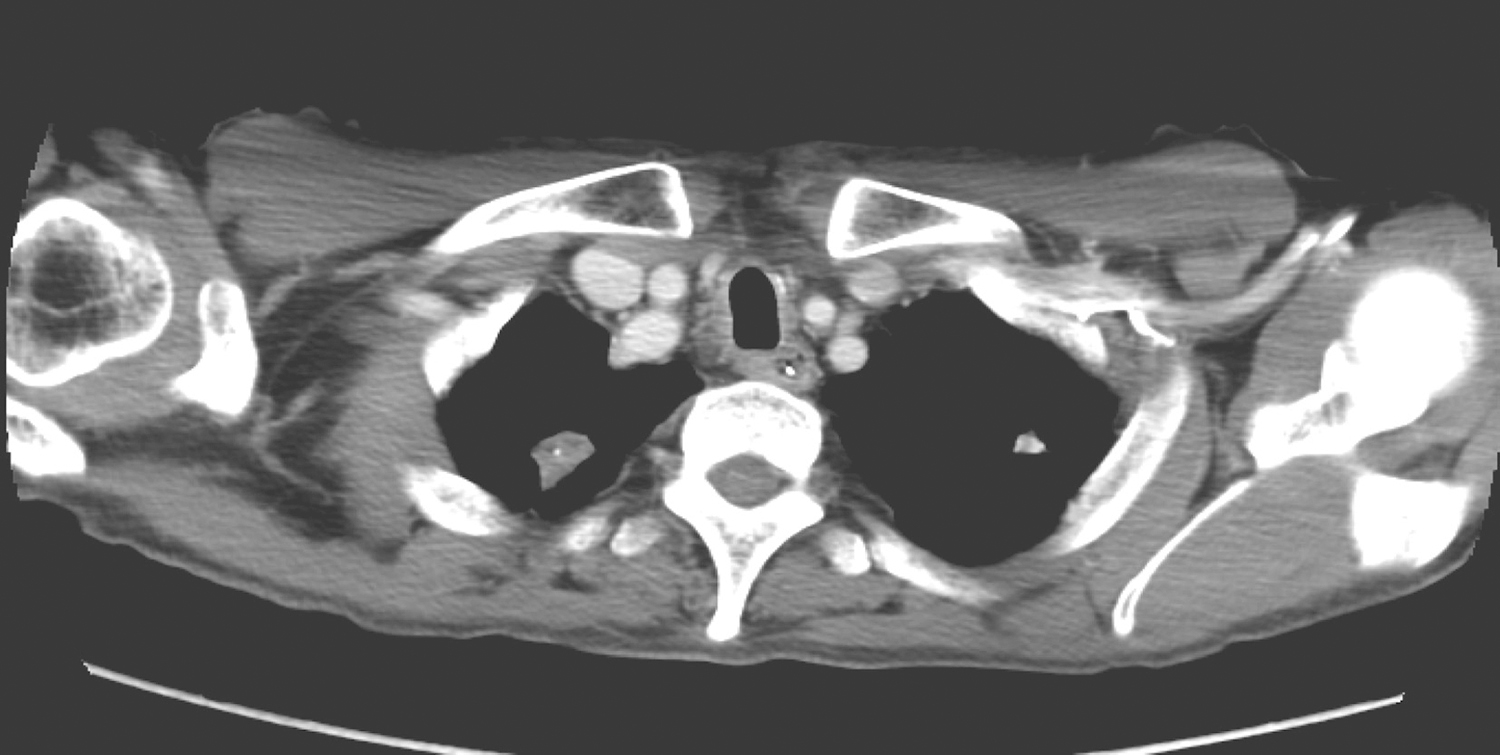

2.2015年1月5日颈胸部CT 参阅2014年10月30日CT检查所见如下:

(1)舌骨、会厌、水平半喉切除、双颈淋巴结清扫、气管造瘘术后改变,局部未见明确肿瘤残留征象,食管内有鼻饲管置入,请随诊。

(2)右上肺新发类结节,形态不规则,边界清楚,密度不均匀,约1.4cm×1.8cm×3.0cm(图5),右上叶后段、左下叶基底段肺新发少许极浅淡片影,倾向炎症,请结合临床考虑,并注意随诊。

图5 右上肺新发类结节,形态不规则,边界清楚

(3)双上肺另见多发小结节及钙化,同前相仿,倾向陈旧性病灶,请随诊。

(4)双肺弥漫泡性肺气肿,同前相仿。

(5)双侧颈部、腋窝、胸内未见异常肿大淋巴结。

(6)未见胸腔积液或心包积液。